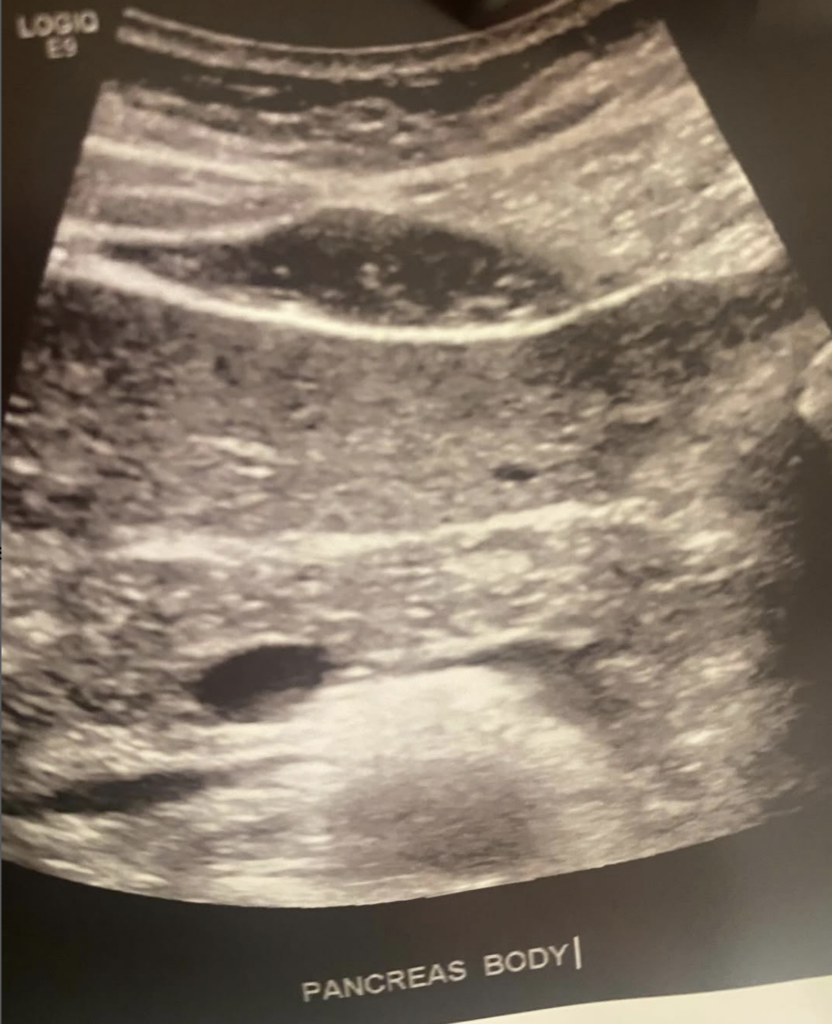

Gillian’s TPIAT

Gillian Redman